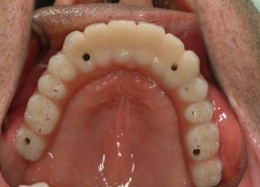

最低4本のインプラントを埋入し、それらを連結し、半日で固定式の仮歯まで入れて審美性、機能性を一日でとりもどせる革新的な治療。

2.歯の形はほぼ天然歯があった時と同じになるので取り外しの義歯に比べて違和感がなく、手入れもインプラントの本数を少なくすることにより、清掃もし易くなっています。